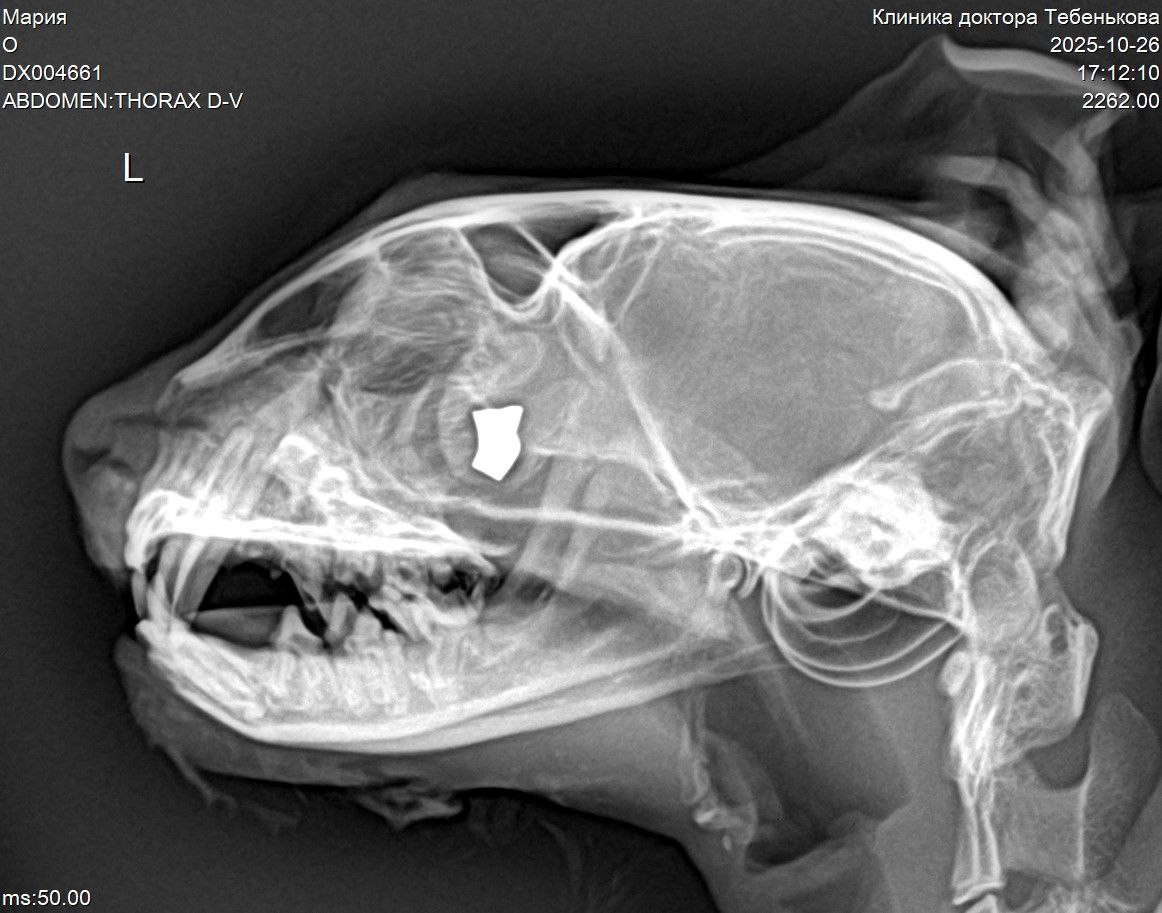

Благотворительный фонд «Клякса» сообщает о тяжёлом состоянии новой подопечной — кошки по кличке Мария. Её привезли в ветеринарную клинику, где в голове животного обнаружили глубоко застрявшую пулю.

Как выяснилось при более пристальном осмотре, выяснилось, что основной риск для жизни и здоровья Марии представляет пуля в её голове. При этом, по словам специалистов, извлечение пули на данный момент невозможно из-за тяжёлого состояния животного.

Выстрел какого-то негодяя привёл к серьёзному повреждению — у Марии диагностировали несостоятельности верхнего неба. Но это не единственная проблема. У кошки выявлен ряд серьёзных заболеваний: анемия, гепатобилиарные нарушения, глистная инвазия и блохи. И это выявилось ещё до полной диагностики, которая сейчас невозможно по той же причине, что и хирургическая операция по извлечению пули.